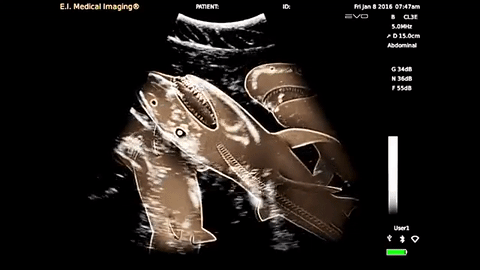

Can you imagine? Congratulations – you’re having SHARKS! You’re looking at the first ever shark ultrasound. Scientists were shocked to discover the shark, who they named “Emily,” was really pregnant.

The 12.5 foot tiger shark was found with 20 well-formed thrashing pups – which incidentally comes with 20 tiny jaws of razor sharp teeth! Scientists estimate the shark pups to be about 40 to 45 centimeters (15 to 18 inches) long. That delivery sounds delightful.

James Sulikowski, of the University of New England, along with collaborators from the University of Miami conducted the sonogram in the Bahamas. Their ultrasound is groundbreaking because, not only is it uncharted territory, it could also change how researchers study pregnant sharks. Shark wombs used to be cut open in order to be studied, which ultimately killed the mother.